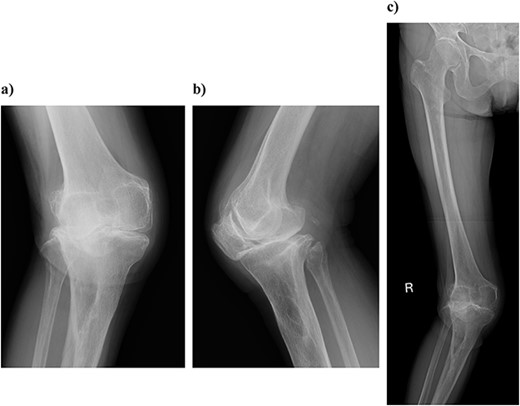

On physical examination, the patient extension and flexion were − 20° and 130°. A defect of the tibial tubercle was observed. The Knee Society (KS) score was 44 points, and the Knee Society function (KS-F) score was 70 points. A plain radiography showed valgus knee osteoarthritis assessed as Kellgren–Lawrence grade 4. In addition, a well-defined translucent image of bone appeared near the central part of the proximal tibia and no tibial tubercle could be observed (Fig. 1). Magnetic resonance imaging (MRI) of the right knee joint showed the patellar tendon appeared from the attachment on the patella with continuity to the tibial bone marrow in T1- and T2-weighted imaging (Fig. 2).

Preoperative simple magnetic resonance imaging: (a) lateral side and (b) axial morphism. T1- and T2-weighted images continuous from the patellar tendon attached to the patella both show continuity from the low signal area to the inside of the tibial bone marrow.